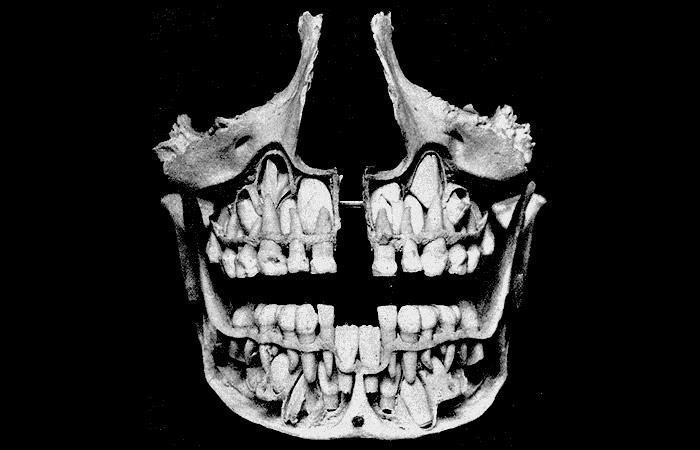

4. No, It’s Not Some Creature, It’s Actually The Inside Of A Human Mouth

One of the ways by which new parents are able to discern the growth of their young one is by constantly keeping a hawk-like watch on whether or not they reach their milestones. One of those milestones is them getting their teeth. Now, as you all would know that we first get, what is known as milk teeth, and then as we age, our permanent teeth start to come in (3).

A lot of us are under the impression that the new teeth grow in a similar fashion as a plant, with seed sprouting to become a full-fledged plant. But here we are, telling you that your permanent teeth were always there, hiding behind your milk-teeth, waiting for their turn (4).